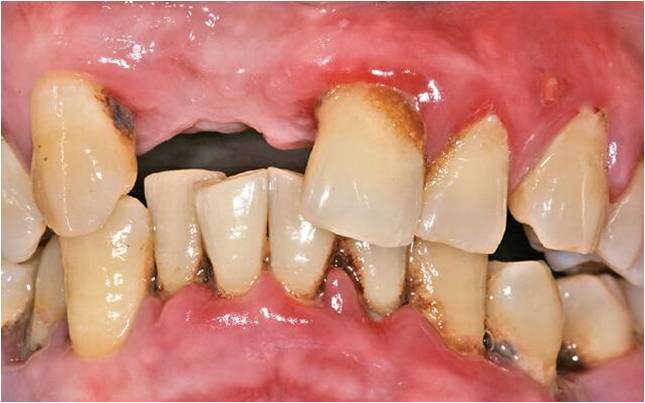

Заболевание пародонта – ответ организма на бактериальную инвазию

Вид больных и протезированых зубов, вы хотите себе такие зубы уже в молодом возрасте.

Общим элементом у всех этих заболеваний есть ВОСПАЛЕНИЕ (в отдельных случаях гноетечение из пародонтальных карманов) → «продлема»: